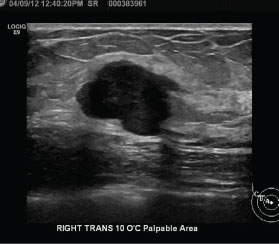

TNBC usually lacks the spiculated margins, irregular shape, and suspicious calcifications associated with other forms of breast cancer. As such, TNBC can be mammographically occult (in up to 18% of cases), despite often being larger than other breast cancers at the time of diagnosis [3]. The most common presentation of TNBC on mammography is a mass [3,10,12,13] (Figure 1). Circumscribed margins are described in approximately one-fourth of cases [3,10,12,13], and there are typically no associated calcifications [3,13]. Less common presentations of TNBC include a focal asymmetry, seen in 10-20% of cases, or a mass with associated calcifications, seen in approximately 15% of cases [11,13]. Isolated calcifications are a much less frequent presentation [10,11]. Dogan, et al. state that mammography alone may have limited value in screening patients at risk for TNBC [3]. These authors indicate that the low incidence of associated calcifications or ductal carcinoma in situ suggests rapid tumor growth that proceeds directly to invasive cancer, without an in situ stage [3].

Figure 1: Mammography findings in triple-negative breast cancer (TNBC). Right mediolateral oblique view with spot compression demonstrates an oval mass with circumscribed margins, representing a biopsy-proven TNBC with necrosis. View Figure 1